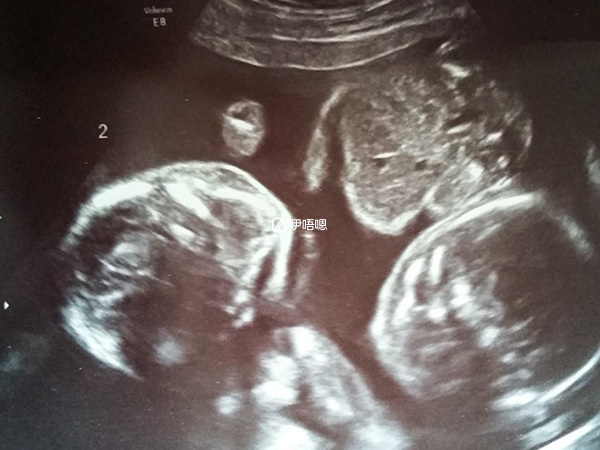

接着又等着一超,这次堵了一个小时的车,我老公送我去医院后就回去上班了。很遗憾,这么个有纪念意义的瞬间不能一起分享了。他发消息问我,到我B超了吗,我说我去拿结果。

然后问他紧张吗,他说他很紧张。我就说你以后要努力搬砖了,他就问我是Twins吗,我叫他猜,他说肯定是的,然后就又开始新一轮报喜了。